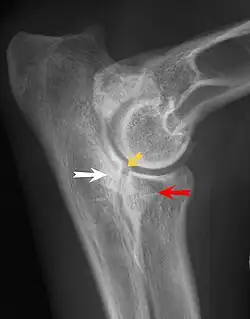

Fragmentation of the medial coronoid process

UAP is caused by a separation from the ulna of the ossification center of the anconeal process.[7] FMCP is caused by a failure of the coronoid process to unite with the ulna.